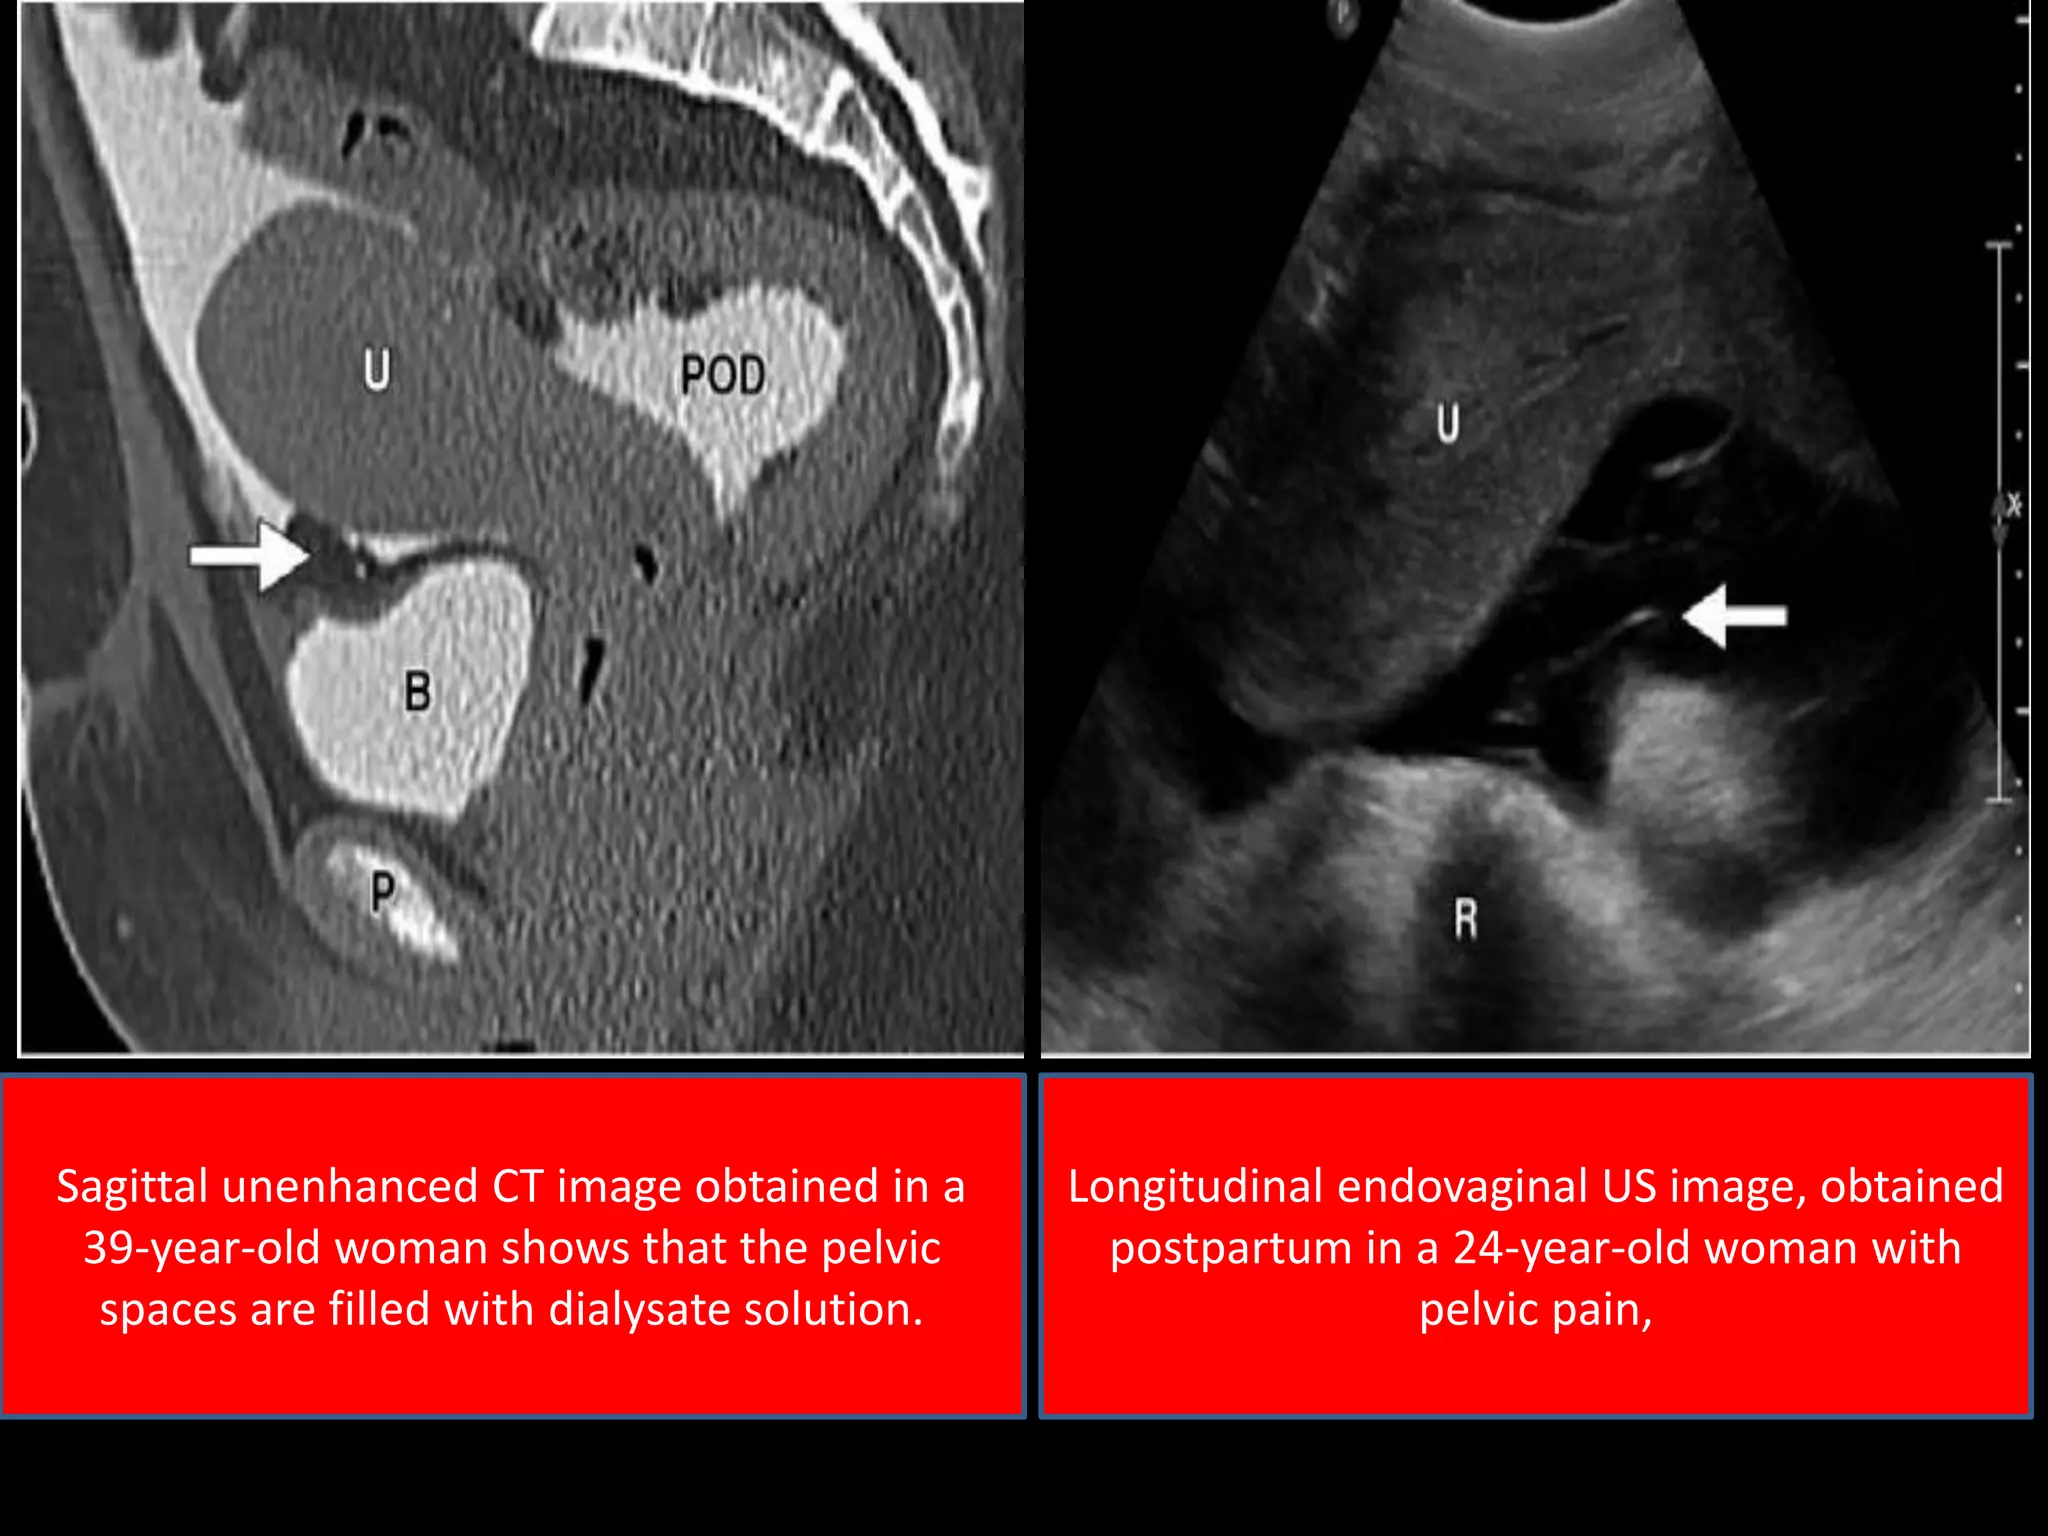

Sagittal unenhanced CT image obtained in a

39-year-old woman shows that the pelvic

spaces are filled with dialysate solution.

Longitudinal endovaginal US image, obtained

postpartum in a 24-year-old woman with

pelvic pain,